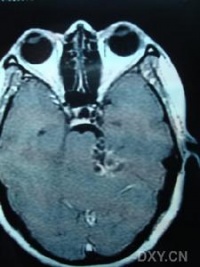

(2)CT及MRI扫描:CT表现为瘤体呈等密度或低密度,少数呈高密度影像。肿瘤多为圆形或不规则形,位于内听道口区,增强效应明显。MRIT1加权像上呈略低或等信号,在T2加权像上呈高信号。第四脑室受压变形,脑干及小脑亦变形移位。注射造影剂后瘤实质部分明显均一强化,囊变区不强化。

(3)CT及MRI检查:目前听神经鞘瘤诊断的标准是Gd-DTDA增强的MRI,特别是当肿瘤很小(<1cm)或在内听道内,CT扫描阴性又高度怀疑肿瘤存在时应该进行GD-DTPA增强的MRI。CT与MRI两种检查有相辅相成的作用,如CT发现有病侧内听道扩大时,增强CT可发现肿瘤对于估计中颅窝入路时颞骨的气化程度及高颈静脉球与后半规管及底的距离有帮助。如果病人已作了CT而肿瘤较大,MRI可提供对脑干压迫的范围Ⅳ脑室是否通畅脑积水、是否存在的情况对可疑听神经鞘瘤或CT检查难于确定时,全序列的MRI可做出鉴别诊断。但也要注意Gd-DTPA的可能假阳性,这与内听道内神经的炎症或蛛网膜炎有关;任何小的接近底部的增强病变应该在六月后作MRI复查,以评估其生长情况。